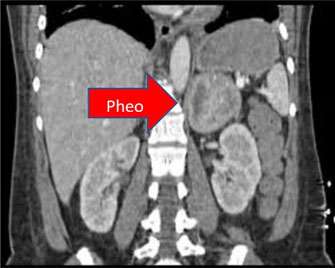

In contrast, approximately 1/3 of pheochromocytoma cases are now known to be genetic, which means that they have a hereditary or familial association. The most common associated genetic conditions are Multiple Endocrine Neoplasia (MEN) type 2 and von Hippel-Lindau Syndrome, followed by Neurofibromatosis type 1 and Familial Paraganglioma Syndrome (which is caused by mutations in the succinate dehydrogenase gene). We recommend genetic counseling for all patients with pheochromocytoma or paraganglioma, as this can provide important information for the patient’s prognosis and earlier screening for family members.

The cause of MEN II is genetic -- a mutation in a gene called RET. Multiple tumors may appear in the same person, but not necessarily at the same time. The adrenal tumor is a pheochromocytoma and the thyroid tumor is a medullary carcinoma of the thyroid. The disorder may occur at any age, and affects men and women equally. The main risk factor is a family history of MEN II.

This syndrome is caused by a mutation in the VHL gene that helps prevent the growth of tumors. Approximately 10-34% of patients with VHL syndrome may develop pheochromocytomas or paragangliomas, in addition to hemoangioblastomas, retinal angiomas, renal cell cancers, and neuroendocrine tumors of the pancreas.